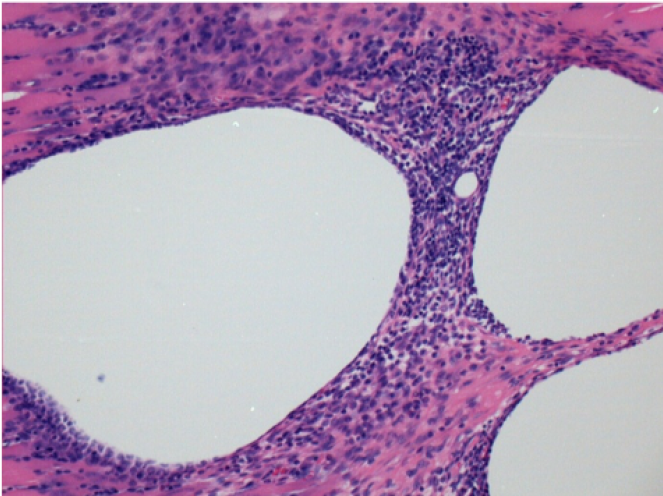

1 mes después de la inyección de Endopeel

1 mes después de la inyección de Endopeel 0,1 ml en el músculo pretibial derecho.

¡Lo que se ve en negro en las imágenes no es una necrosis como podrían imaginar algunos científicos!

De hecho, hay que tener en cuenta 4 conclusiones

- un artefacto de coloración

- una ausencia de necrosis

- una apoptosis

- un proceso biorregenerativo

L : Control-100xD30

R:100xD30

R :400xD30